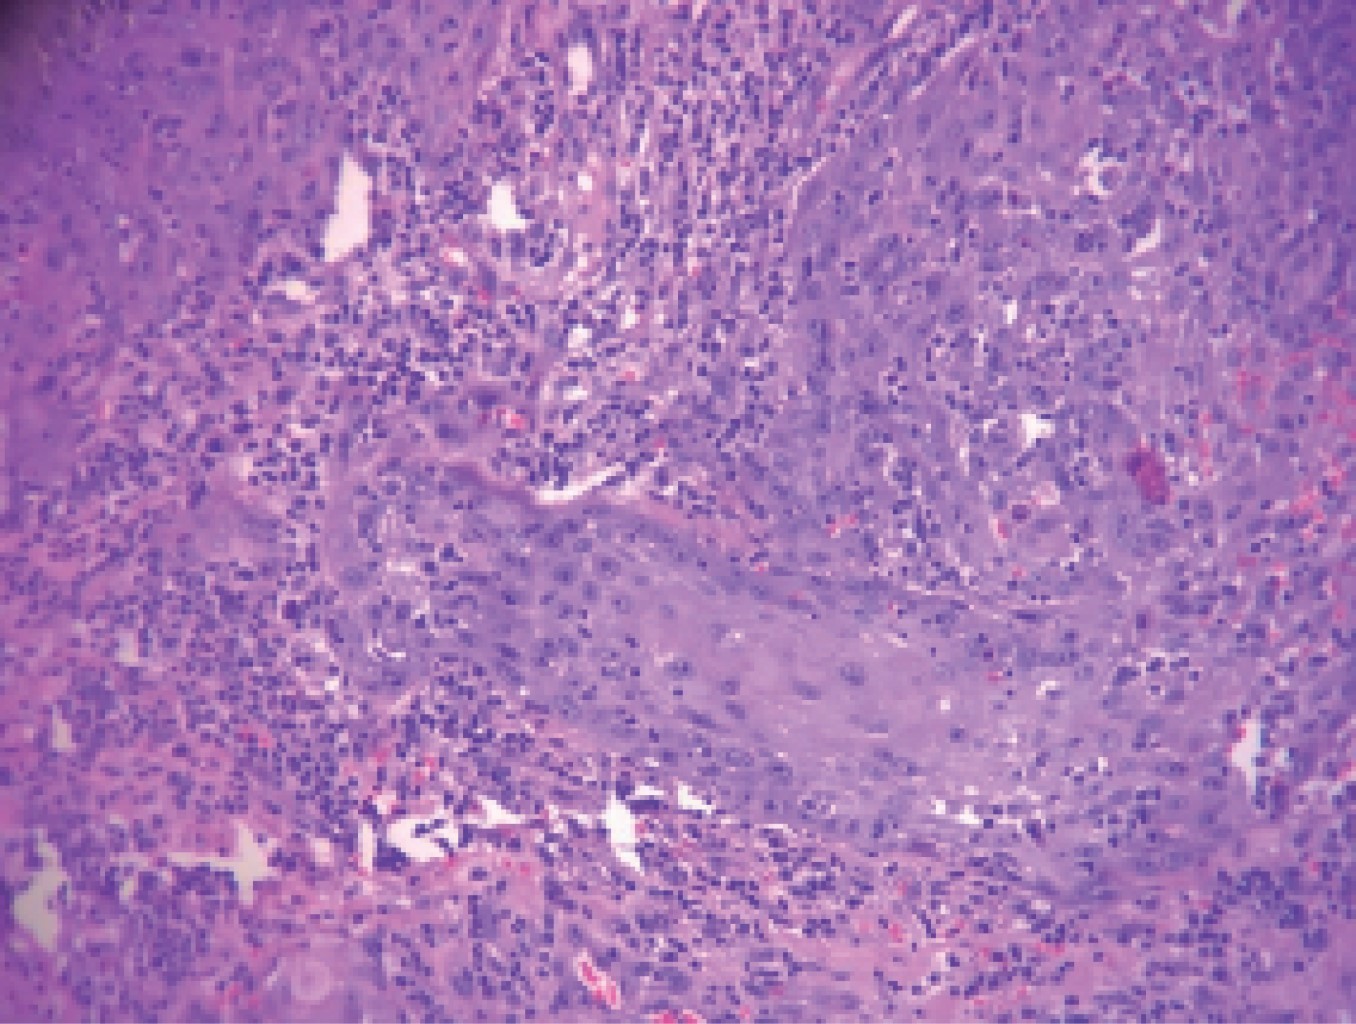

Figure 3